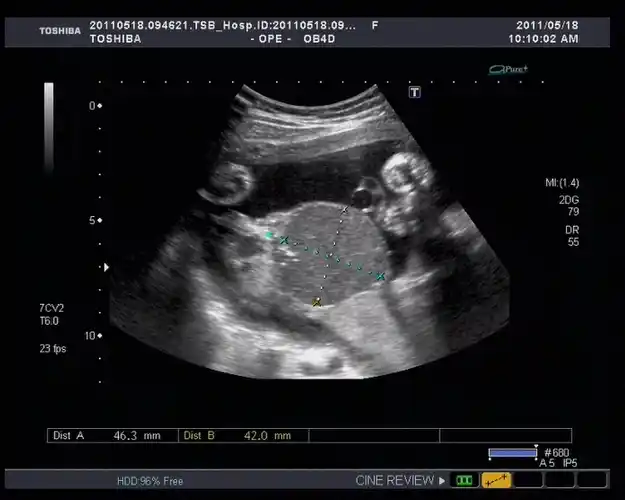

胎盘血池

胎盘血管瘤与血池

胎盘的超声评估_胎儿_前置_子宫